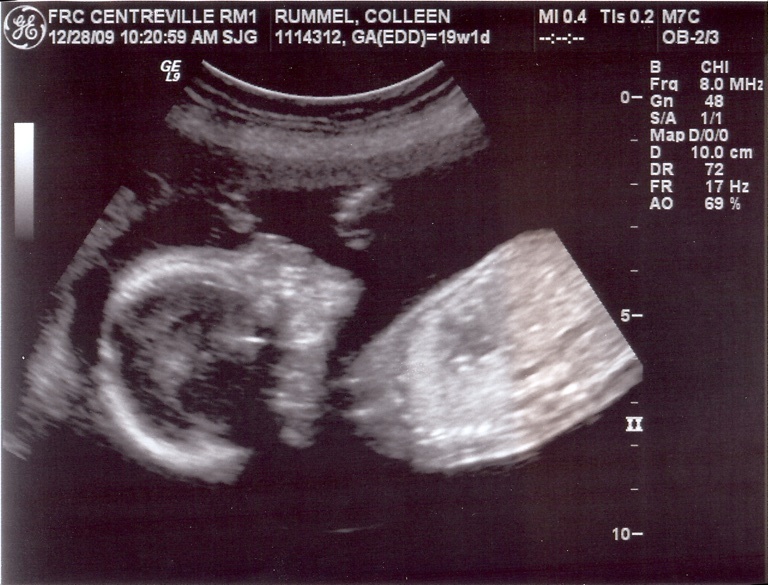

So cute. And if you have to ask what he’s doing back there, you probably don’t want to know.